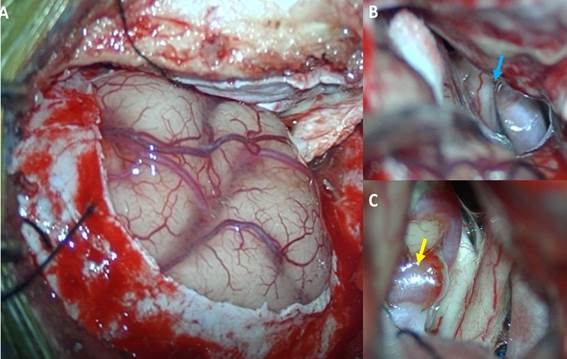

El paciente en posición supina con la cabeza por encima del nivel cardiaco, lateralizada 15 grados. Se realizó un afeitado mínimo de la zona, luego se procedió a una incisión cutánea de 6cm. El colgajo piel-galea se desplazó hacia anterior. El musculo temporal se disecó en su porción antero superior. Craneotomía de 3 x 4 cm, mucho más pequeña que un pterional clásico. Drilado del ala esfenoidal desde la pared orbitaria hacia el ala menor esfenoidal. Apertura de la duramadre en C hacia frontal. Bajo visión por microscopia se inició la disección intradural, llegando a las cisternas basales para liberar líquido cefalorraquídeo y relajar el cerebro, posteriormente se ubicó el aneurisma cerebral (Figura 3). “Clipaje” total del aneurisma con control de angiografía con fluoresceína (Figura 4), observando la patencia vascular de arterias madre y perforantes. Control de hemostasia, cierre dural luego por planos hasta piel.

Figura 3 A: Imagen intraoperatoria, que muestra una mínima exposición parenquimal frontal. B: Liberación de cisternas basales, se evidencia cisterna inter óptica y óptico carotideo (flecha celeste). C: Aneurisma cerebral de arteria comunicante anterior (flecha amarilla).